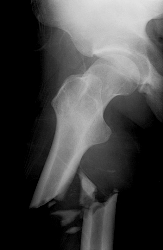

En el Perú, se estima que uno de cada cuatro a cinco hombres mayor de 50 años de edad sufre algún tipo de fractura en el transcurso de su vida a causa de osteoporosis, siendo la fractura de cadera la más discapacitante o causa de muerte en mayores de 60 años, por las complicaciones que provoca el estado de postración en estos pacientes.

Se estima que como consecuencia de esta fractura (de fémur), alrededor del 50% de pacientes mayores de 60 años fallecen dentro del primer año de enfermedad, el 25% presenta algún grado de discapacidad física y sólo un 17 a 20% se reinsertan a su ritmo normal de vida.